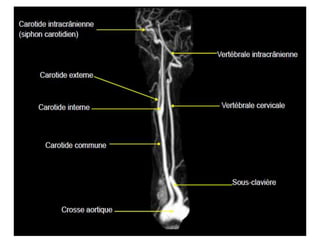

O documento fornece informações sobre como realizar exames de ressonância magnética do pescoço e angiorressonância magnética das carótidas, incluindo parâmetros, programação, anatomia, exames estruturais e funcionais, dicas e protocolos.